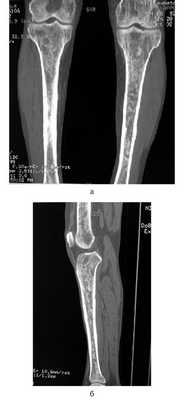

Рис. 5. Множественные остеосклеротические очаги в бедренных (а) и большеберцовых (б) костях.

Из анамнеза: перенес холецистэктомию в 2011 г., наблюдался в поликлинике по поводу ишемической болезни сердца, атеросклероза аорты и коронарных артерий, гипертонической болезни I стадии; аллергологический анамнез без особенностей, наследственность не отягощена. Больным себя считает с марта 2014 г., когда по поводу нарастающей слабости, периодического повышения температуры тела и артериального давления (АД) до 170/100 мм рт.ст. обратился в поликлинику по месту жительства. При компьютерной томографии (КТ) органов брюшной полости и забрюшинного пространства и органов малого таза с внутривенным контрастным усилением омнипаком 350—100 мл выявлены признаки каликопиелоэктазии обеих почек (более выражено справа), инфильтративные изменения стенок лоханок в верхней трети обоих мочеточников, выраженные инфильтративные изменения паранефральной клетчатки с обеих сторон, лимфаденопатия брыжейки тонкой кишки с перифокальной инфильтрацией клетчатки. В легких патологических изменений не выявлено. С диагнозом: болезнь Ормонда наблюдался у уролога и получал терапию 20—30 мг преднизолона. При лабораторном обследовании выявлялась умеренная воспалительная активность: л. (11—15)·10 9 /л; СОЭ 36—68 мм/ч, α 1 -глобулины 7,4% (норма 2,3—6,4%), С-реактивный белок 15,1—35,6 г/л; незначительная гипергаммаглобулинемия до 20% (норма 11—18%) в отсутствие в крови ревматоидного фактора (РФ) и онкомаркеров (ПСА, СА-19—9 и РЭА). Заболевание протекало волнообразно, но в январе 2015 г. у больного появился отек век и стал нарастать экзофтальм. Больной направлен на консультацию в НИИР. При осмотре: кожа век пигментирована. На веках ксантелазмы различной величины (см. рис. 1). Лагофтальм 3 мм справа и 4 мм слева. Ограничение подвижности глазных яблок во всех отведениях. Конъюнктива век, переходных и полулунных складок отечны. Складка бульбарной конъюнктивы вдоль всего края нижнего века с двух сторон. Слезный ручей невысокий, ток слезы замедлен. Пальпебральные доли слезных желез увеличены в размерах, отечны, сосуды резко расширены. Другие органы без особенностей. При ультразвуковом исследовании (УЗИ) щитовидной железы выявлены диффузные изменения по типу хронического тиреоидита. Уровни гормонов щитовидной железы в пределах нормы, антитела к тиреоглобулину и тиреоидной пероксидазе не выявлялись. По данным магнитно-резонансной томографии головного мозга и глазниц, картина выраженного двустороннего экзофтальма, который может соответствовать периневральной форме идиопатического псевдотумора глазничной клетчатки с воспалительно-отечными (реактивными?) изменениями слезных желез и мышц глазниц. Исследование с использованием ядерного магнитного резонанса головы выявило единичные мелкие очаги в белом веществе головного мозга, вероятно, сосудистого генеза. КТ брюшной полости и забрюшинного пространства. В полости перикарда определяется незначительное количество жидкости, шириной в области переднего листка до 0,7 см. Печень умеренно увеличена в размерах, структура и плотность ее не изменены. Отмечаются выраженное уплотнение и тяжистость паранефральной клетчатки, обе почечные ножки на этом фоне дифференцируются нечетко. На уровне L II —L IV аорта муфтообразно окружена мягкоткаными структурами, толщина которых достигает 1,2 см. Подобного характера изменения определяются и в области нисходящей аорты на уровне T IX —T X . Кпереди от тел нижнегрудных позвонков визуализируется стелящийся инфильтрат толщиной до 1,3 см. В брыжейке тонкой кишки множество увеличенных до 1,8×1,6 см ЛУ без четких контуров. Компьютерно-томографическая картина не противоречит болезни Ормонда. При сравнении с данными от 2014 г. имеется выраженная отрицательная динамика в виде прогрессирования склеротических изменений и явлений гидронефроза с обеих сторон (больше справа), со значительным замедлением экскреторной функции почек. Для исключения лимфопролиферативного процесса целесообразно дополнительное обследование. При УЗИ глаза и глазницы выявлены признаки выраженного отека век и экзофтальма, значительное увеличение размеров изображения, так называемого стандартного плоскостного ультразвукового среза слезных желез «по глубине и ширине» (OD 2,27×1,52 см; OS 2,23×1,03 см). С обеих сторон имеется неравномерное значительное увеличение толщины прямых глазодвигательных мышц, больше с правой стороны (OD 0,52×0,56 cм; OS 0,48×0,53 см). С правой и левой стороны, между зрительным нервом и прямыми глазодвигательными мышцами, имеются области разряжения, которые особенно хорошо видны с внутренней стороны. При иммунологическом исследовании: высокочувствительный (вч) СРБ 105 мг/л (норма 65 г/л), значительное повышение уровня вчСРБ 181,5 мг/л (норма 5 г/л). Выполнено иммуногистохимическое исследование (ИГХИ) биоптата с использованием антител CD138, IgG, IgG4, panCK, CD20, CD3, CD68 (PGM-1). Полиморфно-клеточный инфильтрат представлен множеством гистиоцитов, СD68 + с примесью лимфоцитов, большая часть которых является Т-лимфоцитами, CD3 + . В-лимфоциты в виде отдельно расположенных небольших групп клеток CD20 + . Плазматические клетки CD138 + в большом количестве, большая часть которых является позитивными по IgG плазмоцитами. При реакции с IgG4 позитивны лишь единичные клетки, составляющие менее 10% позитивных клеток по IgG (что можно объяснить, вероятно, предшествующей терапией стероидами). Заключение: учитывая данные анамнеза и морфологическую картину, следует предполагать заболевание, ассоциированное с IgG4. Исследование, выполненное на проточном цитофлуориметре, выявило увеличение процентного и абсолютного количества Т-клеток (CD3 + 89,3%; 2,2·10 9 /л), Т-цитотоксических клеток (CD3 + CD8 + 44,8%; 1,0·10 9 /л), снижение процентного и абсолютного количества В-клеток (CD19 + CD3 – 0,3%; 0,008·10 9 /л). С учетом неэффективности ранее проводимой терапии глюкокортикостероидами (ГКС) больному начата комбинированная терапия ритуксимабом и эндоксаном, которая является оптимальным лечением при IgG4-CCЗ [29—31]. Внутривенно капельно с премедикацией 500 мг солюмедрола введены 1000 мг ритуксимаба и 1000 мг эндоксана 1 раз в 2 нед (2 вливания на курс) с последующим введением эндоксана 1 раз в 14 дней (4 на курс) и поддерживающей терапии метилпреднизолоном 4 мг. При оценке эффективности терапии через 4 мес объективно сохранялся выраженный экзофтальм, периодически отмечался подъем температуры до фебрильной. При лабораторном исследовании отмечено снижение показателей воспалительной активности (Hb 136 г/л, л. 11,5·10 9 /л, тр. 433·10 9 /л, СОЭ 50 мм/ч по Вестегрену (норма до 20 мм/ч), вчСРБ 15,2 мг/л, снижение уровня IgG4 до 2,1 г/л. Наблюдалось полное истощение B-клеток CD19 + в крови. При мультиспиральной КТ (МСКТ) глазниц после внутривенного введения 100 мл визипака в отсроченную фазу в ретробульбарной клетчатке определяется мягкотканое образование с неровными контурами, полностью выполняющее полости глазниц, гомогенной структуры, размерами справа 3,3×4,3×3,5 см, слева 3,3×3,7×3,6 см. Мышцы глаз, слезные железы на этом фоне нечетко дифференцируются. Зрительные нервы окружены мягкоткаными разрастаниями, истончены. Определяется двусторонний экзофтальм. Костно-деструктивных изменений нет. Выполнена МСКТ органов брюшной полости после контрастирования желудочно-кишечного тракта до и после введения везипака. Заключение: проявление ретроперитонеального фиброза. Умеренная двусторонняя пиелоэктазия. Умеренная гепатомегалия. Состояние после холецистэктомии. Незначительный перикардит. Множественные увеличенные ЛУ брыжейки тонкой кишки. При сравнении с данными КТ от 2015 г. без динамики. С учетом прогрессирования клинических проявлений псевдотумора глазниц (см. рис. 2, рис. 3), отсутствия положительной динамики при МСКТ глазниц и органов брюшной полости на фоне терапии, некоторых необычных клинических (периодические подъемы температуры до фебрильной, наличие множественных ксантелазм век) и морфологических (наличие большого количества гистиоцитов и недостаточного количество плазмоцитов, секретирующих IgG4, при ИГХИ для постановки диагноза IgG4-ССЗ) проявлений решено провести дополнительное обследование больного с пересмотром биоптатов для исключения системного варианта гистиоцитоза. Проведена позитронно-эмиссионная томография (ПЭТ) для исключения генерализованного гистиоцитоза. Заключение: данных о наличии агрессивного лимфопролиферативного заболевания, а также другого неопластического процесса не получено. Псевдотумор глазниц, генерализованный фиброз медиастинальный, внутрибрюшной, внутритазовый и забрюшиной клетчатки с минимальным воспалительным компонентом. Изменения по типу «волосатой почки» и «облицованной аорты». Внутрибрюшная лимфоаденопатия, вероятнее всего, реактивного генеза. Двусторонний пневмофиброз, застойные (?) изменения в базальных отделах легких. Двусторонний гидронефроз. Гепатомегалия. Генерализованная мелкоячеистая перестройка костей скелета (остеопороз?). Накопление препарата в скелете, вероятнее всего, за счет раздражения костного мозга (см. рис. 4). При К.Т. нижних конечностей и костей черепа выявлены множественные остеосклеротические изменения в дистальных отделах бедренных и большеберцовых костей (рис. 5) и плоских костях черепа (рис. 6). Сцинтиграфия костей: выявлены множественные склеротические перестройки костного мозга. Симметричная патологическое избыточное накопление радиофармпрепарата (РФП) в костях лицевого скелета, эпифизах, метафизах и метадиафизах трубчатых костей наиболее выраженное в бедренных, большеберцовых и костях стоп. Повышенное накопление в чашечно-лоханочной системе правой почки. Однофотонная эмиссионная КТ/КТ черепа и коленных суставов: очаги патологического избыточного накопления РФП соответствуют склеротической перестройке костного мозга. Пересмотр гистологических препаратов с ИГХИ: среди полиморфно-клеточного инфильтрата большое количество гистиоцитов, пенистых клеток, скопления плазматических клеток. Гистиоциты СD68 + , S100 – , IgG4 + , единичные плазматические клетки. Субстрат поражения может принадлежать гистиоцитозу, учитывая локализацию следует предполагать БЭЧ (см. рис. 7). Методом полимеразной цепной реакции в реальном времени с анализом кривых плавления (Rotor Gene 6000) выполнено молекулярное исследование биоптатов. В 599—601-м кодонах 15-го экзона гена BRAF мутация не обнаружена. На рис. 8 представлена частота повторяющихся клинико-радиологических находок у больных БЭЧ, согласно данным литературы и в нашем случае заболевания. Таким образом, больному диагностирован генерализованный гистиоцитоз: БЭЧ с конституциональными нарушениями (лихорадка, патологическая утомляемость, снижение массы тела), поражением кожи и области глазниц (ксантелазмы век, экзофтальм, псевдотумор глазниц, дакриоаденит), костей (остеосклеротические поражения бедренных, малоберцовых и плоских костей черепа), поражение сердечно-сосудистой системы (выпотной перикардит, поражение грудной и брюшной аорты по типу «облицованной аорты»), ретроперитонеальных проявлений (гидронефроз, пиелоэктазия за счет инфильтрации околопочечной ткани по типу «волосатой почки») c отрицательной мутацией BRAFV600E.